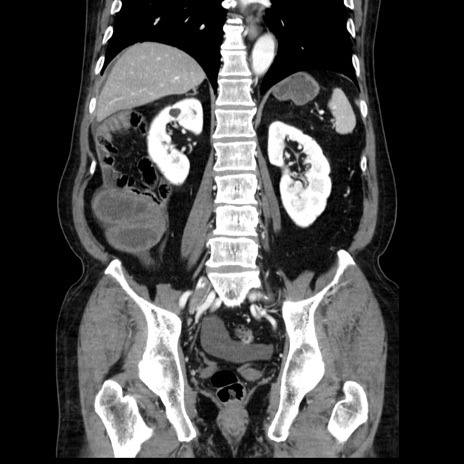

症例30(冠状断像)

【症例】80歳代男性

【主訴】臍周囲痛

【現病歴】約6時間前から臍下部痛が出現。次第に腹部膨隆・背部痛も生じてきたため来院。背部痛の場所は変化しない。

【既往歴】腎盂腎炎

【身体所見】意識清明、BT 36.3℃、BP  131/87mmHg、P 87bpm、SpO2 100%(RA)、臍周囲自発痛・圧痛あり、反跳痛なし、自発痛部位に一致して板状硬あり、腹部膨隆、腸雑音減弱、CVA tenderness両側陰性。

【データ】WBC 19600、CRP 0.33